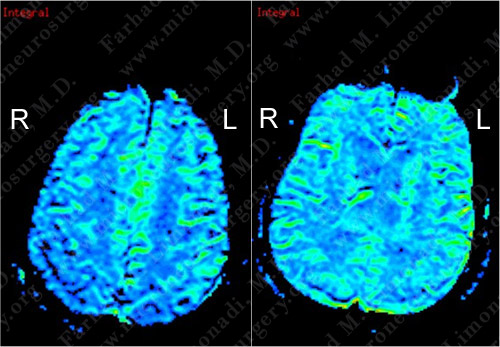

CT SPECT does not show significant hypermetabolism of either of the lesions.